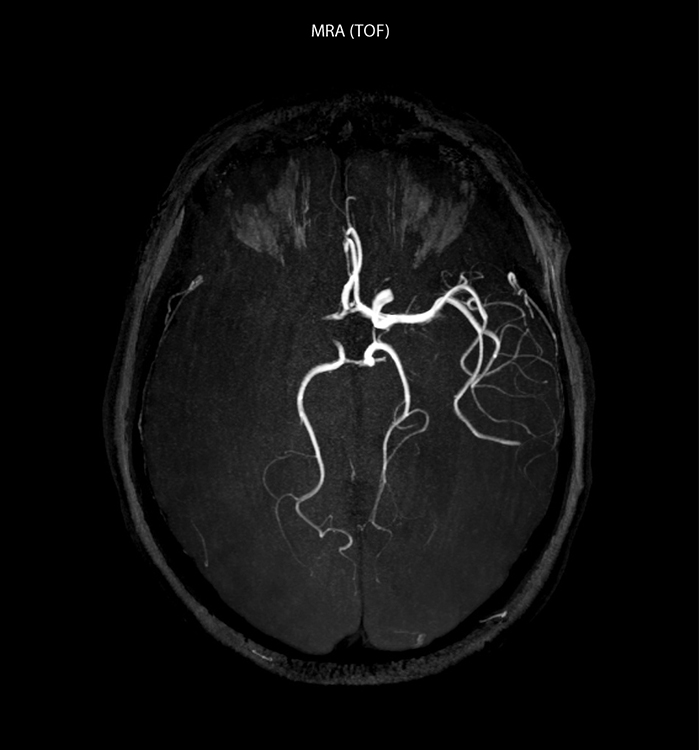

“In France, every stroke is usually imaged with MRI, not CT, even for emergency treatment.” “In France, stroke is usually imaged with MRI, not CT, even for emergency treatment. This is because MRI helps us directly visualize ischemia in the acute phase, but can also help rule out differentials such as MS and hematoma. In addition, we can assess the intracranial and extracranial vessels during the same examination,” says Dr. Savatovsky.

“Ingenia provides great flexibility in the parameters setting. We can tune a sequence the way we want,” says Dr. Savatovsky. “For example, in a stroke exam we use a FLAIR sequence of about two minutes instead of the four-minute FLAIR we use for MS. The diffusion is 30 seconds, the T2*-weighted scan is 30 seconds, the angiography scan time is less than one minute. Ingenia is a great scanner in that situation; even with these fast sequences we can achieve good images with good SNR. When the first sequence tells us that it’s not an ischemic stroke but a hemorrhagic stroke, we may switch to a time-resolved angiography to look for vascular malformations and venous thrombosis.

“Every center is different, but for me the ideal protocol for stroke includes diffusion weighted imaging, FLAIR, and fast susceptibility imaging,” says Dr. Savatovsky. “Our fast susceptibility weighted imaging takes 50 seconds, so it’s as fast as T2*-weighted imaging. It visualizes hemorrhage but also the clots. We also do 3D MR angiography that provides information on cervical and brain vessels. If the patient does not need immediate treatment, or if additional information is needed to decide on treatment, we might also add perfusion imaging and post-contrast T1-weighted imaging.”